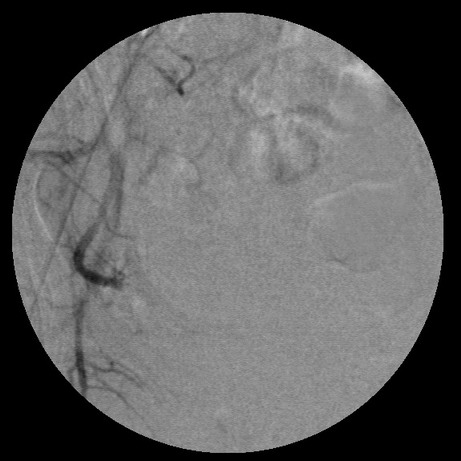

女,35岁,子宫多发肌瘤

左边没有避开卵巢支啊

栓塞剂用的是进口pva,二瓶,几千块呀,栓塞面积应该不大吧,呵呵